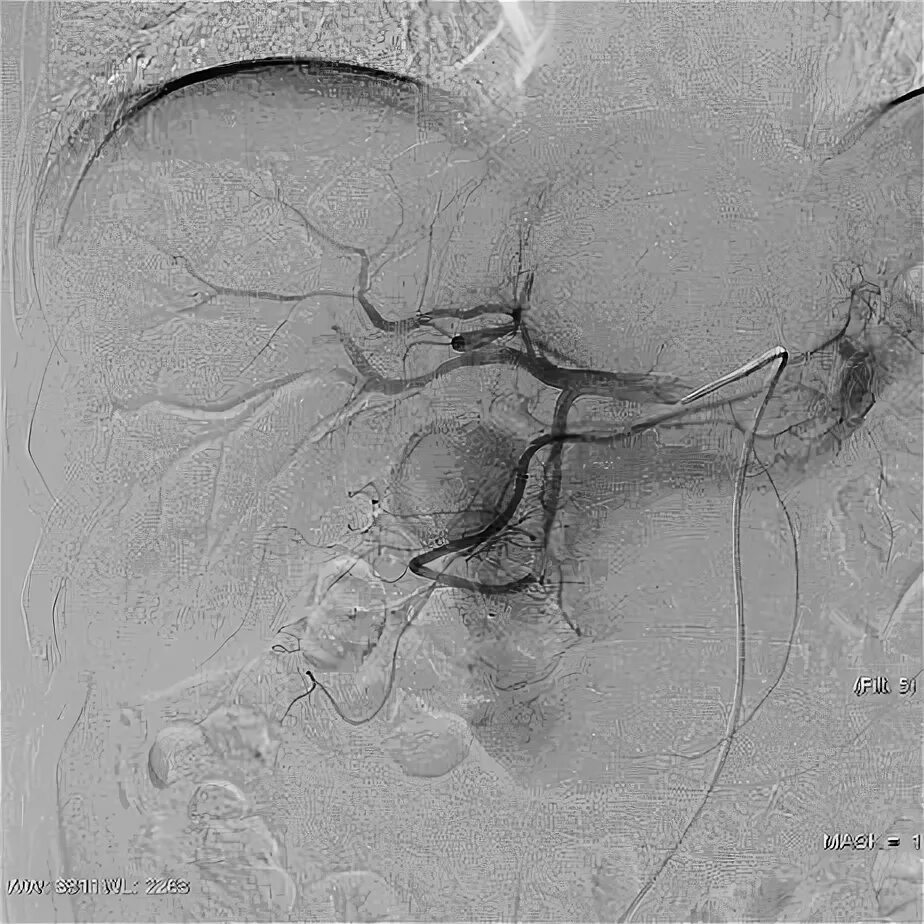

Эмболизация гемангиомы